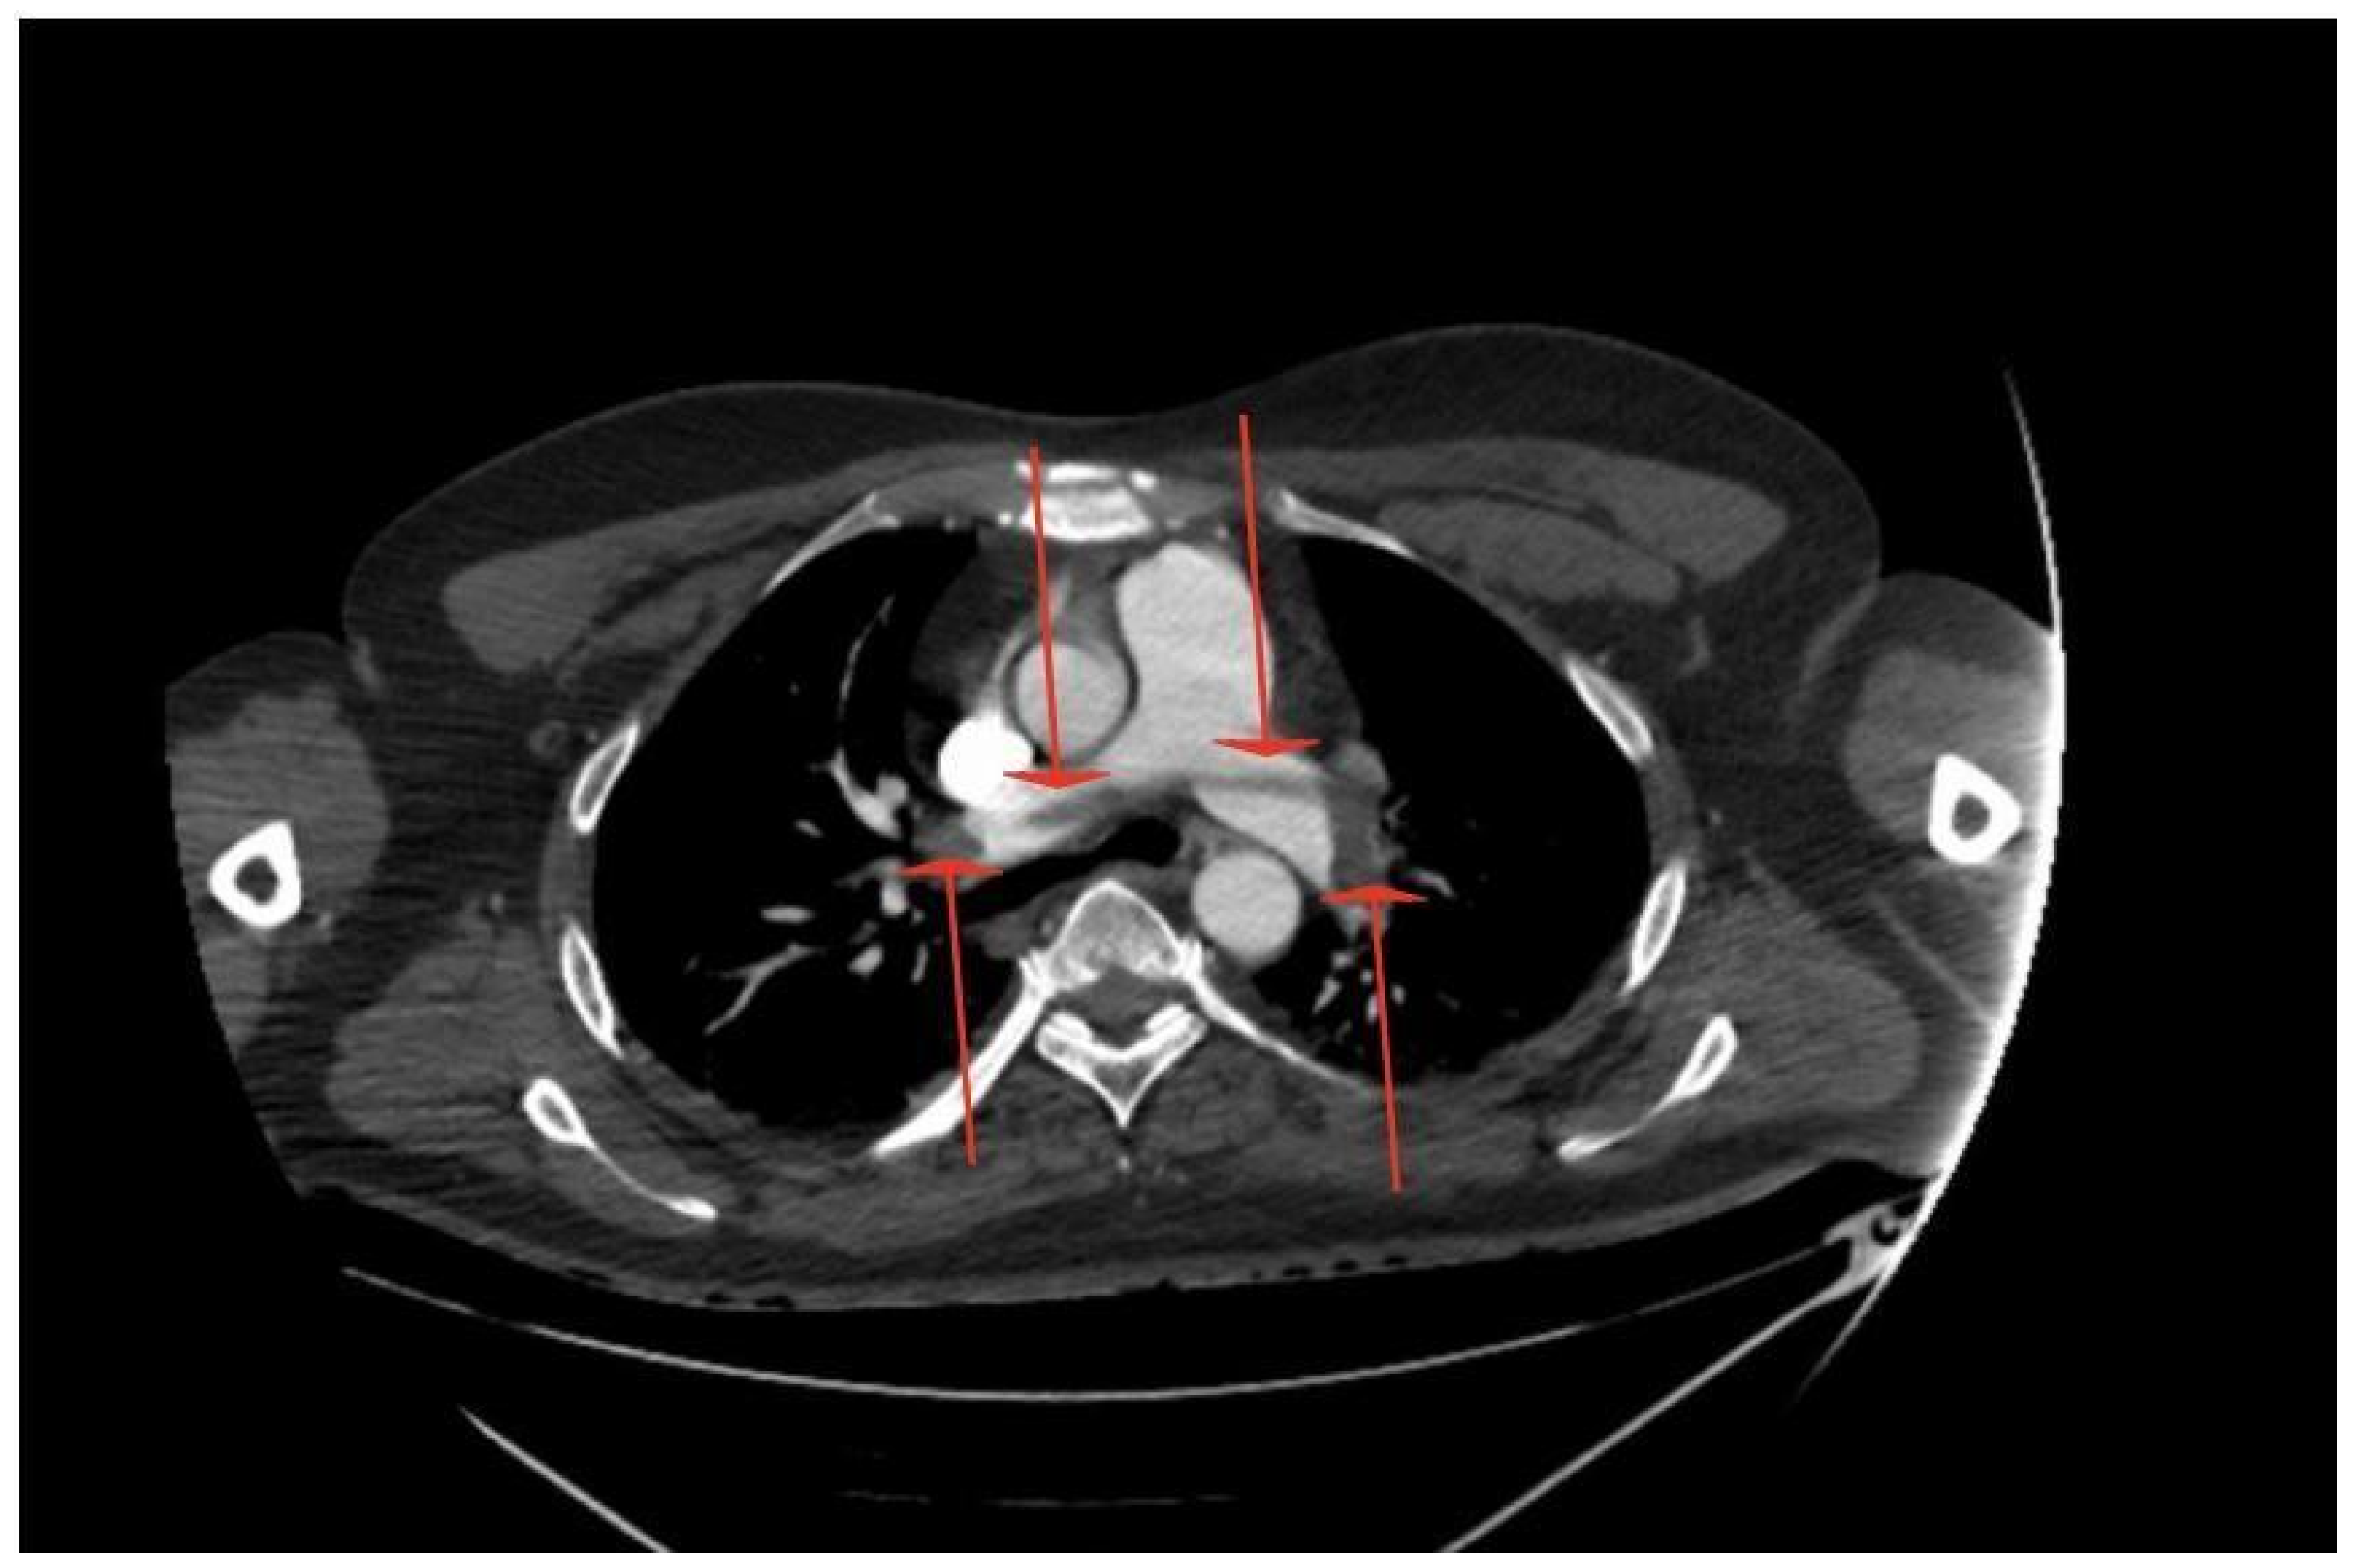

Massive Central Pulmonary Embolism with Riding Embolus and Concomitant Aortic Arch Embolism—Should We Diagnose Patients Earlier for Blood Clotting Disorders? Case Report

2. Case Report